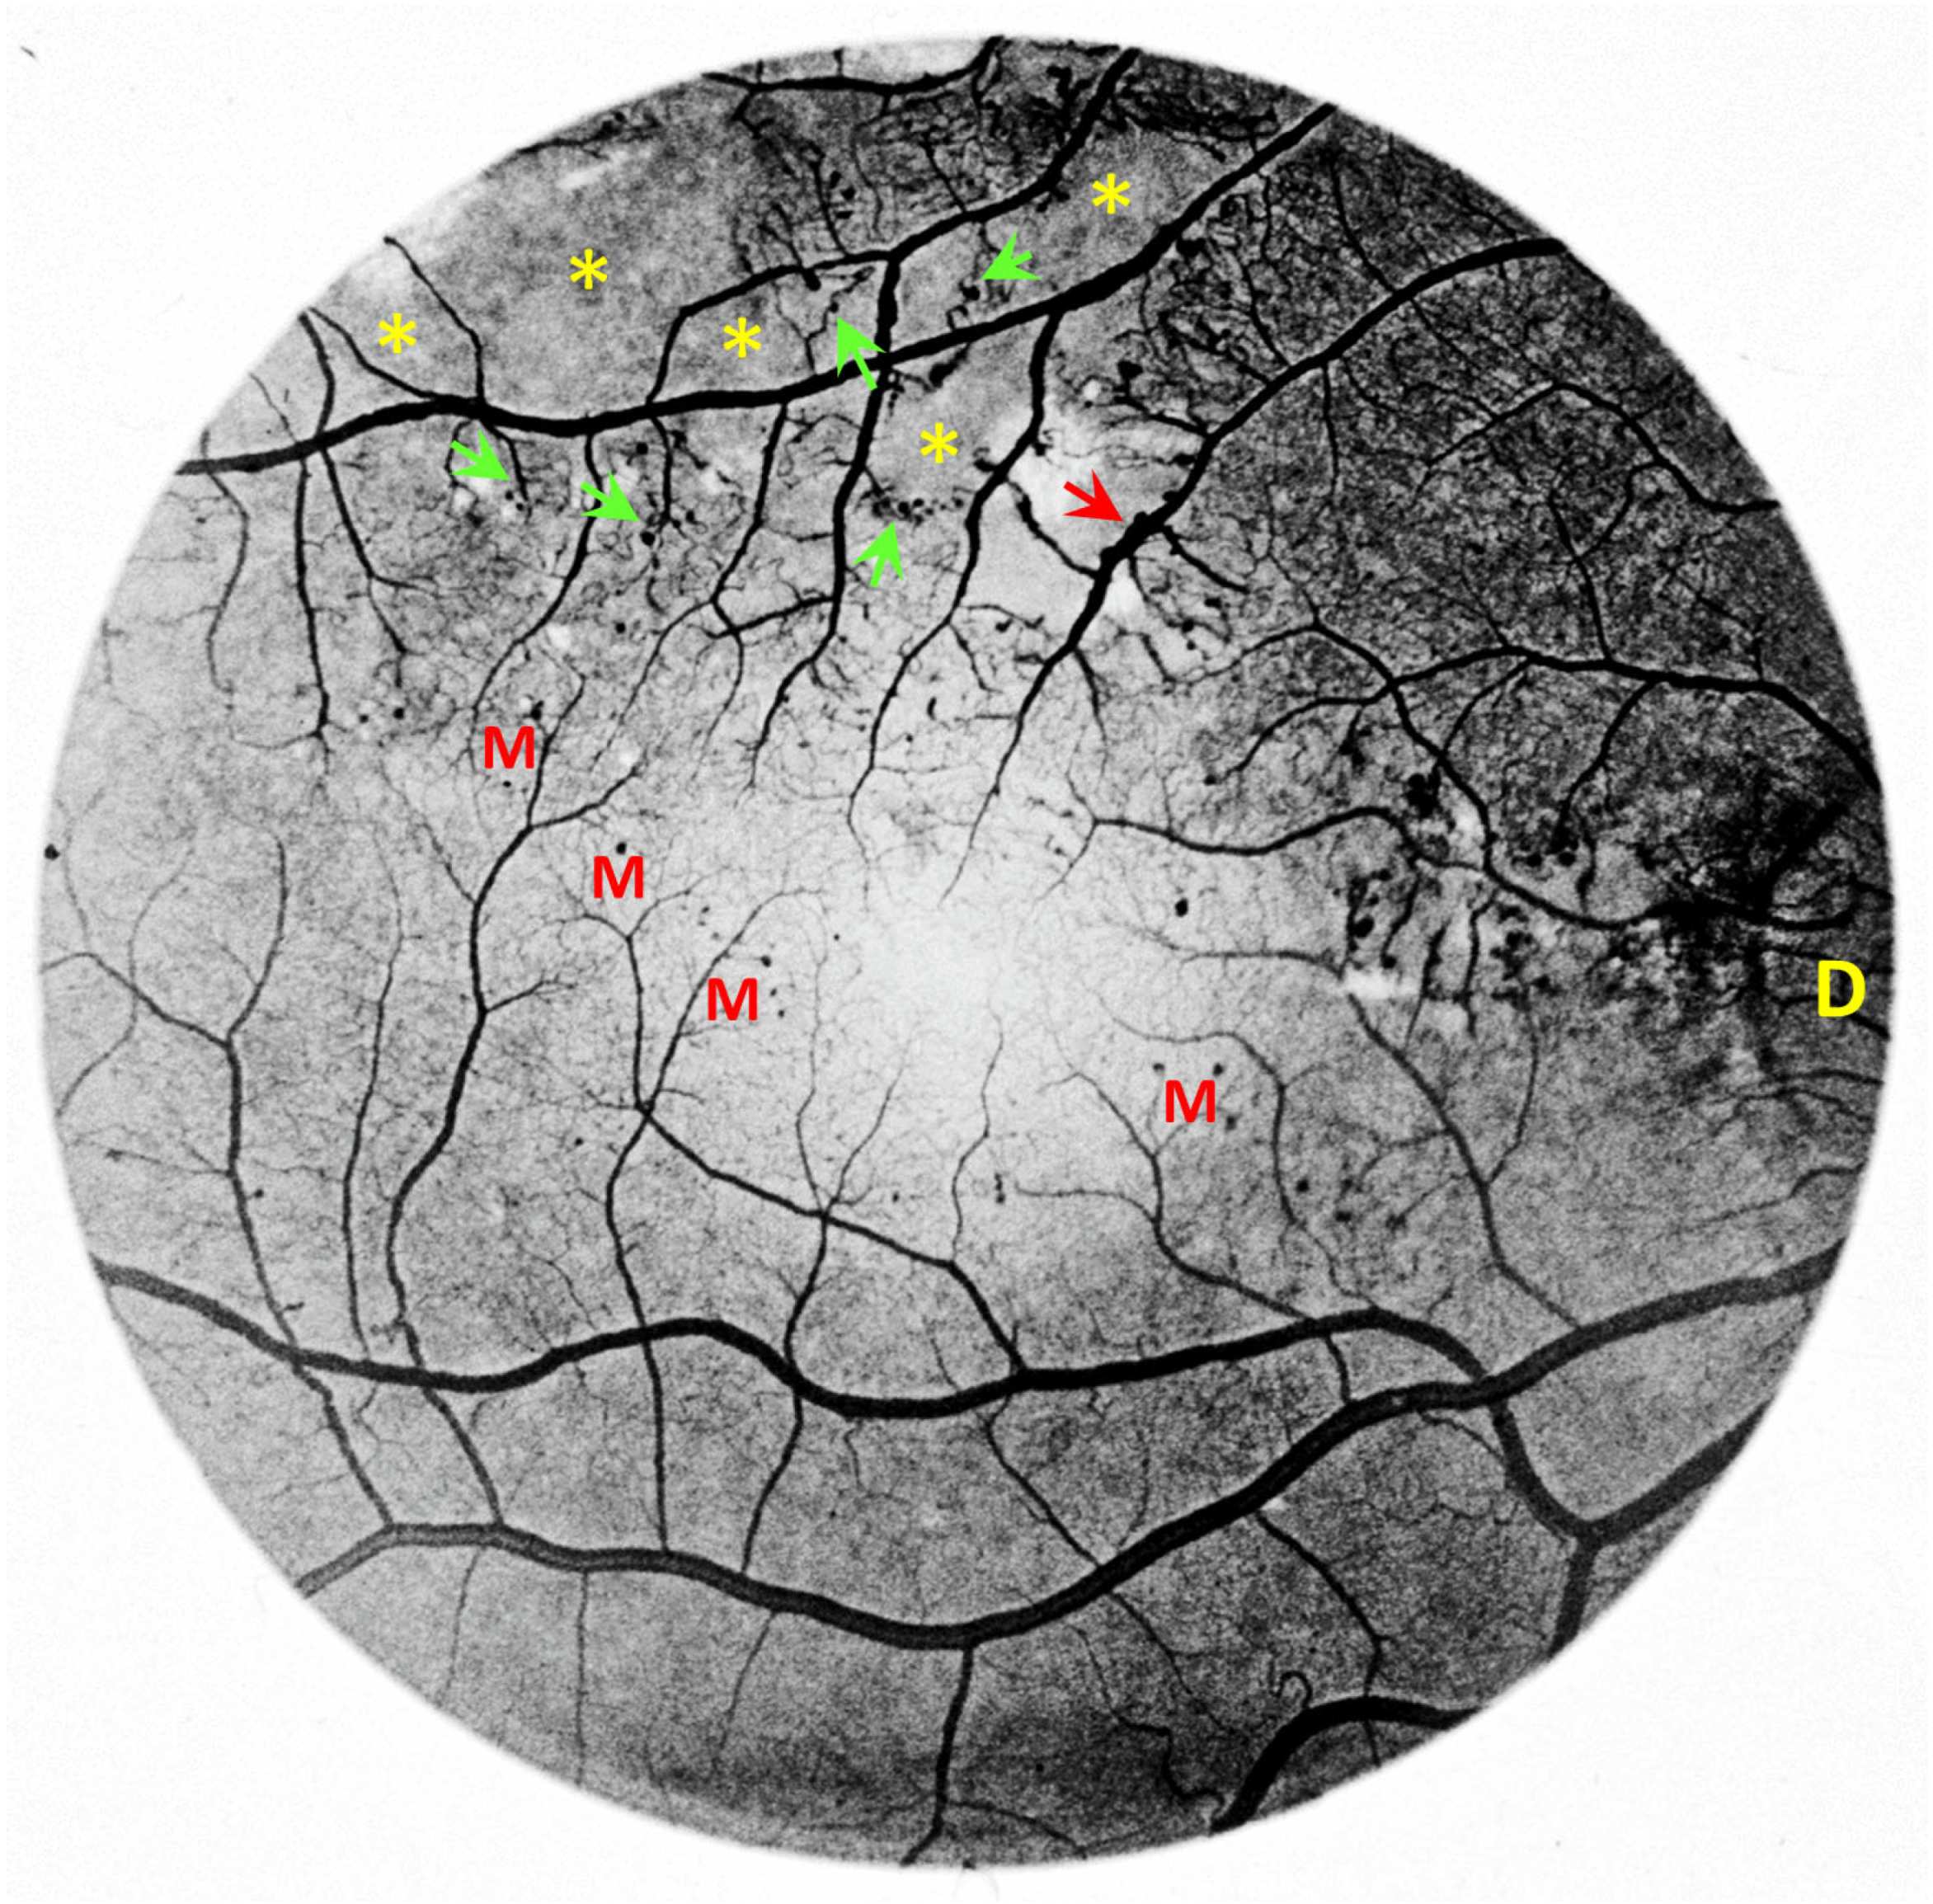

- Amoaku, W.M.K.; Archer, D.B. Fluorescein angiographic features, natural course and treatment of radiation retinopathy. Eye 1990, 4, 657–667. [Google Scholar] [CrossRef]